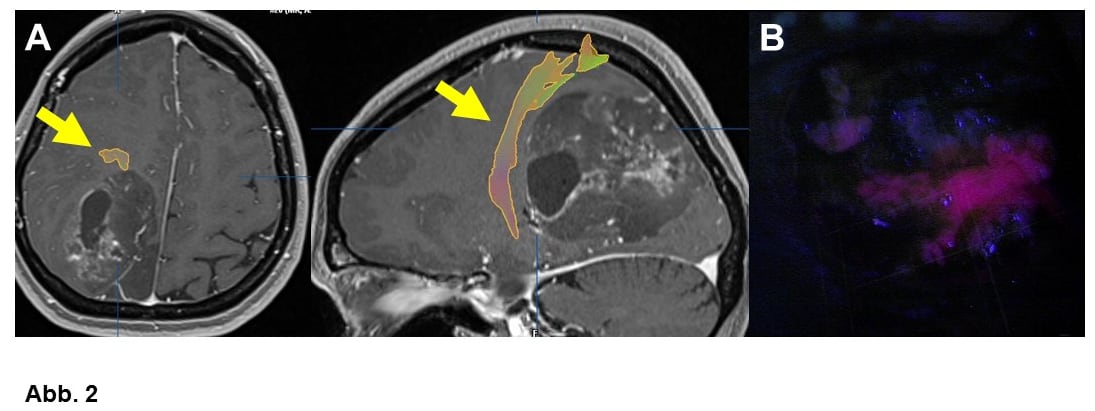

Für nahezu alle Gliome konnte nachgewiesen werden, dass eine Entfernung von Tumorgewebe die Tumorkontrolle verbessert. Daher muss im jeden Fall geprüft werden, ob über eine Gewebsentnahme hinaus nicht auch eine eigentliche Tumorentfernung (Resektion) möglich ist. Um bei einer Tumoroperation wichtige Hirnfunktionen zu schonen, werden vielfältige, zumeist elektrophysiologische (intraoperatives Monitoring, Abb. 5) und manchmal auch bildgebende Techniken (Faserbahndarstellung, Abb. 2A). im Operationssaal eingesetzt. V.a. wenn es um den Erhalt der Sprache geht, wird man ausgewählte Patienten wach operieren wollen (Wach-Operation). Auch bei Tumorresektionen wird die Neuronavigation häufig verwendet. V.a. Glioblastome können mit einem Fluoreszenzfarbstoff angefärbt werden, was ihre Abgrenzung bei der Operation erleichtert (Fluoreszenz-gestützte Resektion, ALA, Abb. 2B).

A. 55-jähriger Mann mit einem Glioblastom WHO-Grad IV. Die sog. Pyramidenbahn, über die willkürliche Bewegungen gesteuert werden, wurde mittels einer speziellen MRT-Technik (fiber tracking) dargestellt (Pfeile). Solche Bilder können für die Neuronavigation genutzt werden, so daß man bei der Operation ziemlich genau weiß, wo die Faserbahn verläuft. Ganz ähnlich kann man auch Teile der Sehbahn und bestimmte für die Sprache wichtige Bahnen darstellen.

B. Fluoreszenz-gestützte Operation: Im Fluoreszenzlicht färbt sich nach Einnahme von ALA kurz vor der Operation Glioblastomgewebe in aller Regel violett.